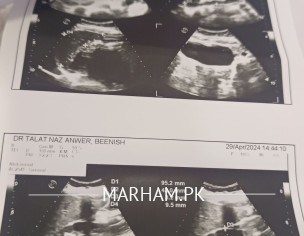

Asking For Self, Female 33, Karachi

mere report mein fitty changes aayi hy Kiya matlb hy iska please

Pls share the report then I can comment

Attach Photo here: